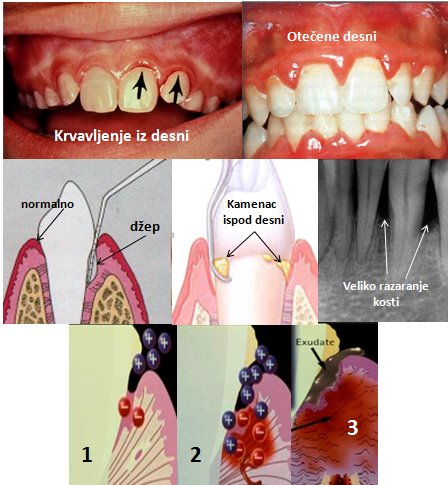

Parodontopatija je hronično inflamatorno oboljenje potpornog aparata zuba,to je deo tkiva koji okružuje zub i daje mu čvrstinu i stabilnost.Ovo oboljenje dovodi do razaranja parodontalnog tkiva i posledicno do gubitka zuba.

Prva i najčešća faza bolesti je upala desni (gigngivitis), koja, ukoliko se na vreme ne leči, prerasta u parodontopatiju, zahvata kost oko zuba i kasnije dovodi do pomeranja, labavljenja i napokon ispadanja zuba.

Cilj terapije parodontopatije je eliminisanje mikroorganizama iz parodontalnog džepa. Blaži oblici, kao što je upala desni, mogu se sasvim neutralisati uklanjanjem naslaga i kamenca, uz adekvatnu edukaciju pacijenata o održavanju oralne higijene.Zatim uklanjanjem supragingivalnih i subgingivanlnih naslaga oko zuba i u parodontalnom džepu.

Ako je parodontopatija uzela maha, ukoliko su prisutni parodontalni džepovi i gubitak koštanog tkiva, što se može uočiti kliničkim pregledom i analizom digitalnog radiograma, potrebno je pored kauzalne terapije ciscenja takvih dzepova i uklanjanja naslaga,primeniti i hiruske metode lecenja.